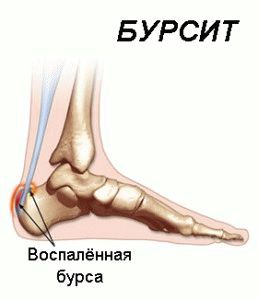

Бурсит є досить неприємним і болючим запальним процесом, який вражає суглобові сумки, або бурси, а також п'яту. Будучи ізольованими порожнинами з тонкими стінками, такі сумки відповідають за зниження тертя і за захист суглобів, м'язів і сухожиль під час травми, але самі можуть піддаватися інфікування, подразнення і травматизму (трапляється це під час високих навантажень).

На сьогоднішній день фахівці розрізняють кілька видів бурситу області п'яти:

- запалення ахіллового сухожилля (п'ятковий або ахиллобурсит),

- подпяточний запальний процес.

Різновидом вищевказаного захворювання є подпяточний бурсит, який є запальним процесом п'яткової синовіальної сумки, яка знаходиться під шкірою. В даному випадку область п'яткової бугра починає стрімко і болісно набрякати. Подпяточний бурсит може бути спровокований також і іншими, не менш серйозними причинами. Крім тривалих навантажень і незручного взуття, причинами розвитку запалення можуть виявитися наступні проблеми зі здоров'ям людського організму: